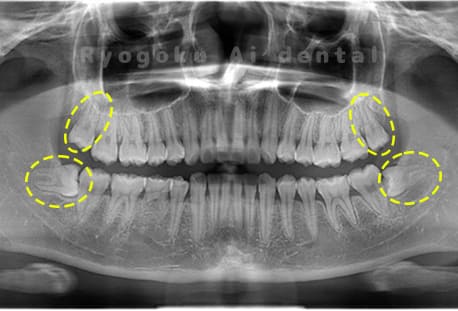

Case03

-

- 原因

- 上顎、下顎の親知らず

- 治療内容

- 上下4本の親知らずを抜歯したケースです。

<リスク・副作用>

手術後は痛み、腫れ、痺れなどの副作用が生じる場合があります。